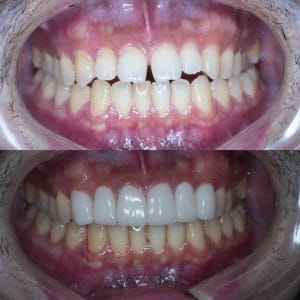

Case029

セラミック矯正の患者様です。

・上下の歯の入れ違い

・正中の歪みと隙間

を主訴にご来院くださいました。

この患者様は若年性歯周炎にかかってしまったため、一生懸命に歯を磨き、口の中は綺麗なのにも関わらず歯茎が下がってしまい、隙間が出来てしまっています。

これは矯正治療で歯の並び方を変えても絶対に無くなりません。

そのため、患者様の主訴を叶えるためにセラミック矯正で治療計画を練りました。

前のクリニックでは「上下一本ずつ抜糸してブリッジで矯正する」という計画だったようですが、

・患者様が非抜歯を希望されていること

・歯を抜かなくても綺麗に並べられそうだったこと

を理由に、当院では上は抜かずにセラミック。下は形態修正だけで対応しました。

この方針変更だけでもお値段も安く、また侵襲(ダメージ)を少なくすることができました。

治療の結果、最低限の侵襲で、見違えるほど綺麗な口元に治療することができ、患者様もとても喜んでくださいました。

主訴とご希望によって、ワイヤー矯正、マウスピース矯正、セラミック矯正のどの矯正が適しているかは異なります。

当院では上記全ての治療法に対応することができるので、主訴とご希望に沿った方法で治療することが可能です。

カウンセリングにてご希望をお伺いした後、一つ一つの治療の違い、当院のおすすめをご紹介いたしますので、ご希望の治療方法をお選びいただけます。

歯並びなどお口元にお悩みのある方、より綺麗な口元になりたい方はぜひ一度ご相談ください。

【主訴】

・上下で入れ違っている前から2本目の歯のすれ違いを治したい。

・清潔感のある白さで明るい綺麗な口元にしたい

・歯の隙間を無くしたい

【ご要望、ご状況】

・歯を抜かずに治したい

・前医では上下1本ずつ抜歯をして、ブリッジで上3本、下3本の計6本を治すことを提案された。

【今回の治療法】

・右上の犬歯から左の前歯までの計4本をジルコニアセラミックで治療

・色は自分の歯よりやや白いくらいでホワイトニングをしてもしなくても大丈夫なくらいの白さ

・歯は抜かない

・右下の歯は形態修正だけで対応

・歯茎のラインを歯肉整形術で整える